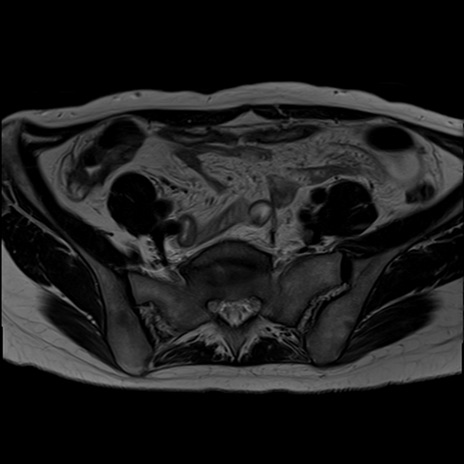

症例39 T2WI(横断像)

MRI(4日後)